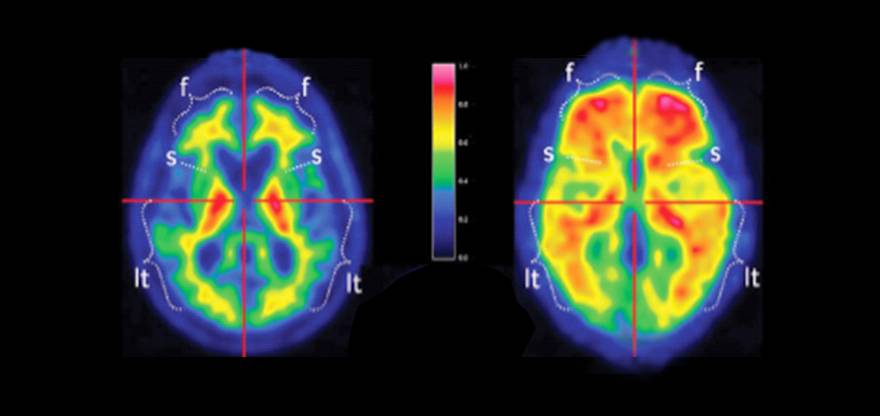

Izquierda: imagen PET cerebral donde se aprecia en rojo la placa beta-amiloide de una persona sana; derecha, placa en una persona con Alzhéimer.

En el caso del Parkinson, los biomarcadores más importantes "son aquellos que se realizan con estudios de Medicina Nuclear que permiten observar el metabolismo de la dopamina que puede alterarse en fases muy precoces y nos ayuda a diferenciar el Parkinson de otras enfermedades", sostiene el doctor Rafael Arroyo, que explica que caso de la enfermedad de Alzheimer se conoce que entre 15 y 20 años antes mostrar sus primeros síntomas existen alteraciones cerebrales: "La detección de ciertas proteínas, como la beta amiloide o la Tau en el líquido cefalorraquídeo o a través de estudios de PET cerebral son los biomarcadores más destacados para un diagnóstico tempano y certero de la enfermedad".